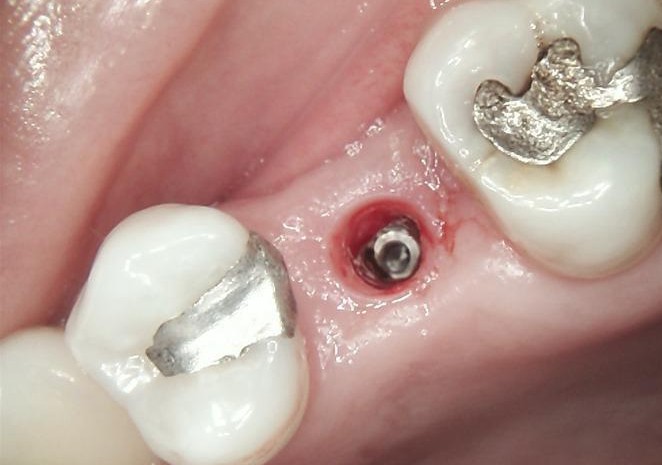

FINAL

After successful osseointegration, the definitive restoration was delivered using a Ti-base-supported crown, held by Dr Carmy.

Final radiographic evaluation confirmed proper implant positioning and bone stability.

The treatment resulted in a functional, stable, and esthetically harmonious restoration fully integrated with the adjacent dentition.